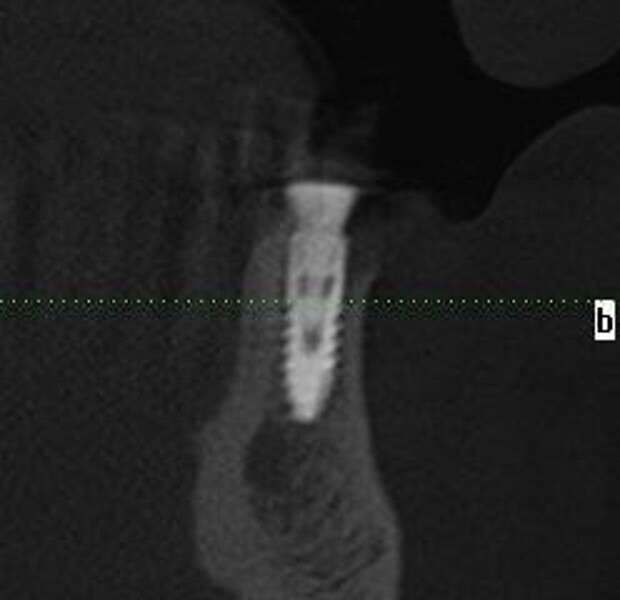

Implantacja z wykorzystaniem szablonu nawigacyjnego 3D